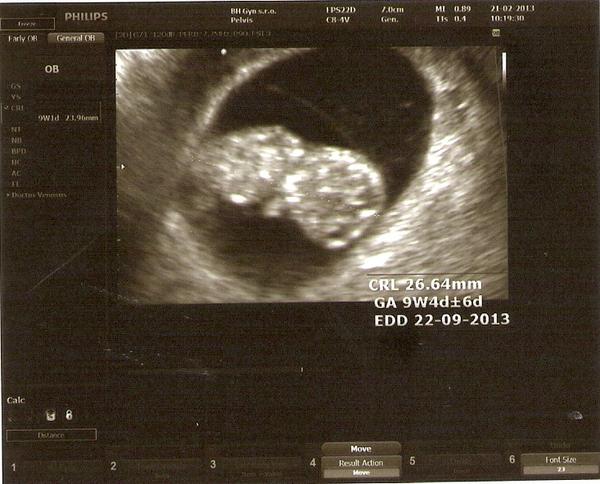

@fidka21 dorazí za 9 mesiacov . 😀